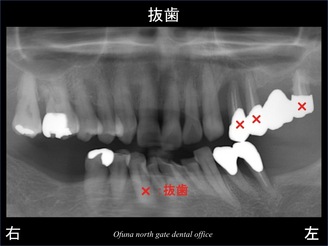

本日の症例は、『上顎の左側の奥歯がグラグラしている!』とのことで来院されました。

この時すでに

下顎の左右の奥歯 もありませんでした。

上顎の左側の奥歯がグラグラしていました。

指で触っても 取れそうなくらいです。

以下のレントゲンの赤丸が問題となっている歯です。